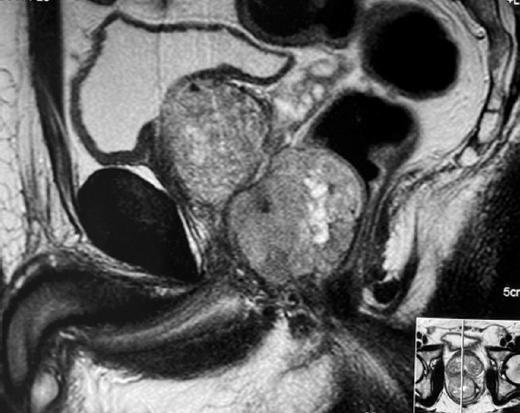

Los GIST rectales representan la tercera localización más frecuente, aunque solo suponen el 1.6-5% de todos los GIST34. No tienen síntomas específicos, por lo que frecuentemente se confunden con otras patologías anorrectales. Los síntomas más frecuentes son el sangrado (28.9%) y el dolor anal (17.8%). En ocasiones son hallazgos incidentales. La TC y la RM (Fig. 4) son muy útiles para su diagnóstico y estadificación, además de permitir determinar una posible afectación de órganos pélvicos. La ecografía endorrectal localiza el tumor y determina el tamaño y su relación con los esfínteres35,36.

Figura 4 Resonancia magnética de tumor del estroma gastrointestinal rectal que permite apreciar sus relaciones anatómicas en pelvis.

La elección del tipo de cirugía debe individualizarse según el estado del paciente, la localización y tamaño del tumor, el grado de la extensión e invasión local y la experiencia del equipo quirúrgico35,36. La resección quirúrgica puede ser muy dificultosa en situaciones de pelvis profunda y estrecha, tal y como ocurre en varones; o en caso de tumores muy próximos a esfínteres anales u otros órganos vecinos. En estas condiciones, la resección R0 solo se llega a conseguir en un 40-60% de los pacientes.

Los GIST rectales localmente avanzados, no candidatos a una cirugía de resección «de entrada», deben someterse a tratamiento neoadyuvante (Fig. 5) para reducir su tamaño y facilitar la preservación esfinteriana40,41. La combinación de neoadyuvancia y cirugía es factible en más de la mitad de los casos40,41.

Figura 5 Efectos del tratamiento neoadyuvante en tumor del estroma gastrointestinal rectal, antes (izquierda) y después (derecha) del tratamiento con imatinib, apreciándose una importante disminución del tamaño tumoral.